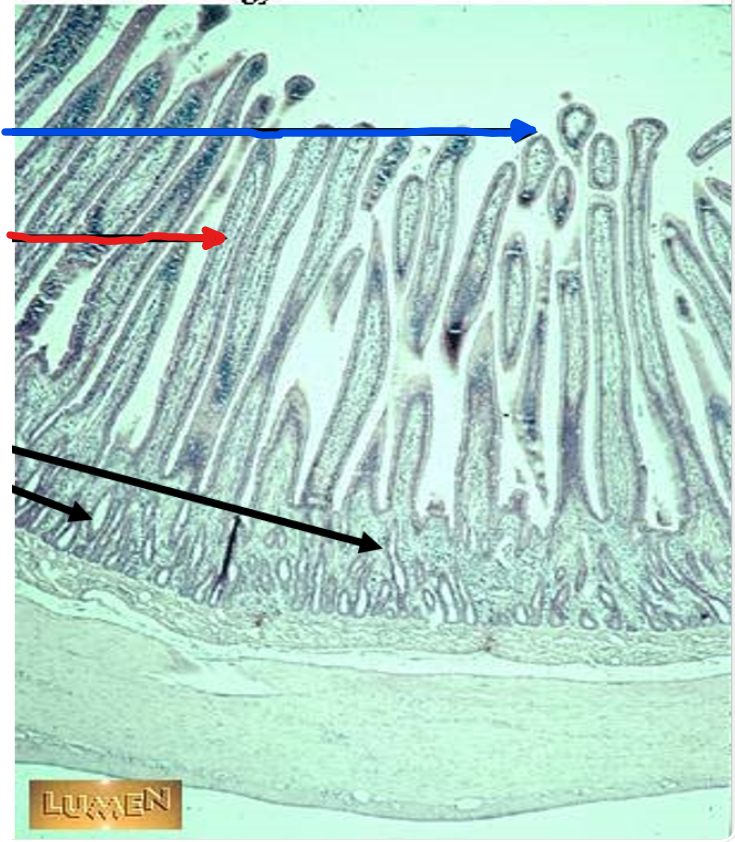

plicae circulares

green

villi

crypts

blue

lamina propria

black

simple columnar epithelium

the blue arrow

the red arrow

the black arrows

this is in the

jejunum